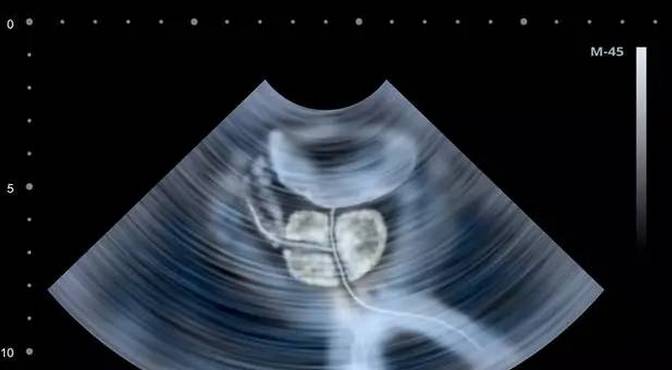

前列腺处于膀胱和尿道之间,尿道好像苹果柄从前列腺中间穿过,如果前列腺增生,就会将尿道压住,影响排尿。